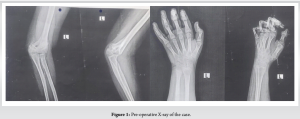

Later X-ray was done which showed 6-month-old supracondylar fracture (Figure 1) and diagnosed VIC of the left upper limb, moderate degree based on Tsuge classification (Table 1). Patient was treated with analgesics, antibiotics and other supportive measures. Later under general anesthesia Max Page release surgery was done (Fig. 3). Post-operatively antibiotics, analgesics were continued and good correction was seen at 6months follow up (Fig. 4). A splint was applied to maintain correction (Fig. 5).